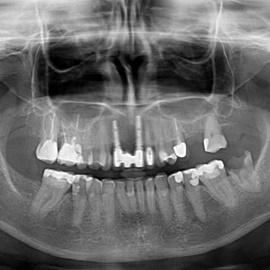

Pacjentka po ekstrakcji kilku zębów, z implantacją natychmiastową, odroczoną. Zdjęcie pantomograficzne wykonano pięć lat po implantacji. Widoczna stabilna sytuacja kostna i dziąsłowa.